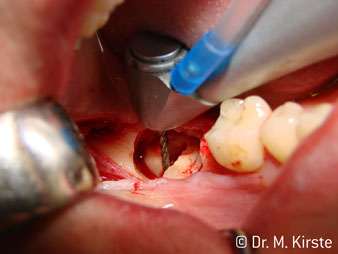

The 45° angle of the handpiece has been specially selected for its wide range of advantages. Colleagues who work in surgery, and for whom this handpiece was primarily developed, will soon appreciate the ability to work efficiently in very restricted spaces. In wisdom tooth extractions in particular (fig. 2) there is no need for large-scale spreading of the soft tissues in the cheek region (fig. 3). The design of the handpiece head combined with turning the head slightly during preparation allows work to be carried out quickly and safely in the retromolar region.

Speaking of working quickly: the instrument can achieve up to 100,000 rpm while a very professional cooling system and small attachment head cover all aspects relating to thermal effects and unobstructed work.

The professional design of the bearings inside the handpiece head guarantees quiet running of the bur; this makes for an impressively atraumatic cut in the separation of tooth and root (fig. 4-9).